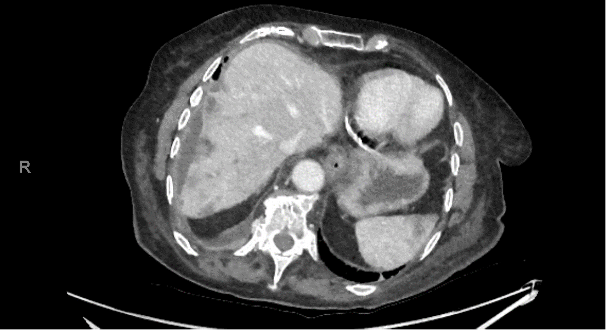

Une patiente de 90 ans consulte les urgences en raison de douleurs abdominales et de vomissements. L’abdomen est diffusément douloureux, particulièrement en hypochondre droit. Le bilan biologique montre un important syndrome inflammatoire avec des leucocytes à 33 G/L et une CRP à 250 mg/L, sans perturbation des tests hépatiques. Un CT-scanner abdominal est effectué.

Le radiologue retient des probables abcès hépatiques en raison du syndrome inflammatoire sans exclure un diagnostic différentiel de métastases. La patiente est hospitalisée pour antibiothérapie iv.